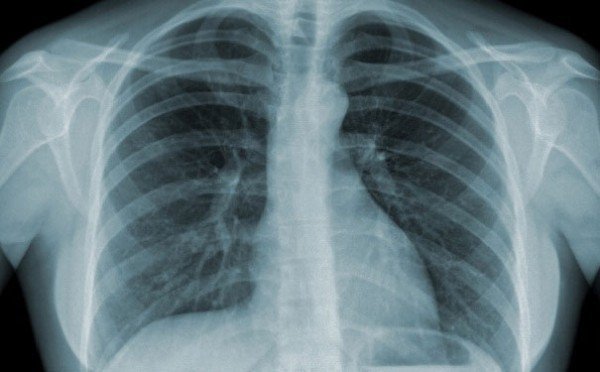

Chụp X quang là một thuật ngữ khá phổ biến và quen thuộc trong y học. Vậy X quang là gì và chụp X quang để làm gì? Dưới đây là 22 câu trả lời về các vấn đề liên quan đến bức xạ tia X, cũng như những lợi ích đi kèm rủi ro của chúng.